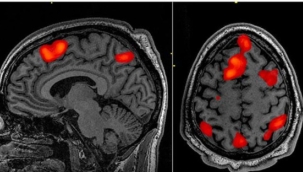

Covid-19 beynin küçülmesine neden oluyor

Ölüm anındaki beyin aktivitesi ilk kez kaydedildi

Beyinde "matematik nöronları" bulundu

Covid-19 akıl sağlığını olumsuz etkiliyor